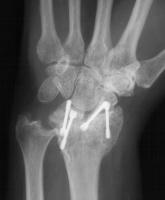

Three months postop :

Image Image Image